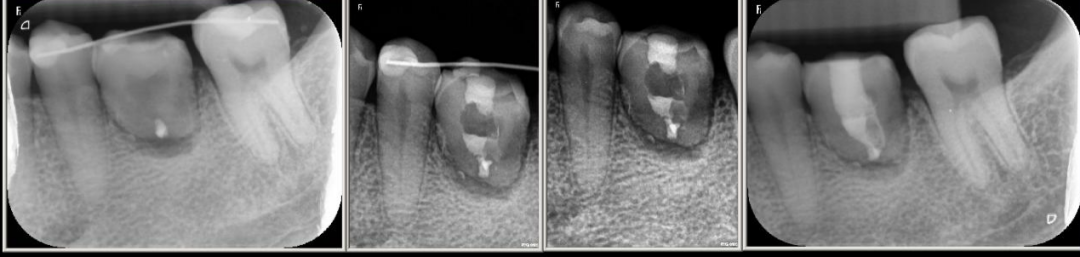

然而,随着计算机技术的高速发展,自体牙移植技术聚集了目前大部分口腔先进治疗技术,如微创拔牙术、牙槽骨及牙周组织再生技术、数字化导板技术和种植技术等等,目前成功率可以达到86.67%,存留率达96.67%。有学者进行15年随访,成功率可以达到81%,存留率达88.37%。本科室组织口腔各科室专科专家进行术前讨论,已通过计算机数字化辅助技术,利用3D打印技术制作智齿模型,在数字化导板引导下精准备洞,调整空缺位置,给智齿建成一个合适的“新家”,给它一次做有用牙齿的机会。本科室对自体牙移植具有丰富的经验,预后较好,获得了患者的认可和好评。